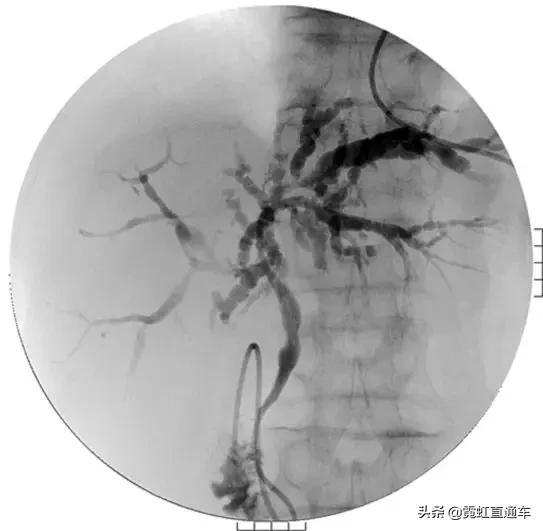

3、PSC影像学表现(日本厚生劳动省官网提供)

ERCP:胆管狭窄与扩张交互,呈串珠状改变

多发短小狭窄,胆管环状受累

PTCD:胆管呈边缘不整羽毛状

ERC:胆管壁呈憩室样突出